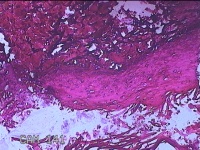

左侧肘后包块

性别

男

年龄

58岁

临床诊断

皮下结节

一般病史

发现左侧肘后包块半个月余,无明显疼痛及不适。

标本名称

大体所见

灰白暗红色带皮肤样包块1.5x1.3x0.3cm一个,表面糜烂,切开包块呈实性,切面灰白暗红色,质软。